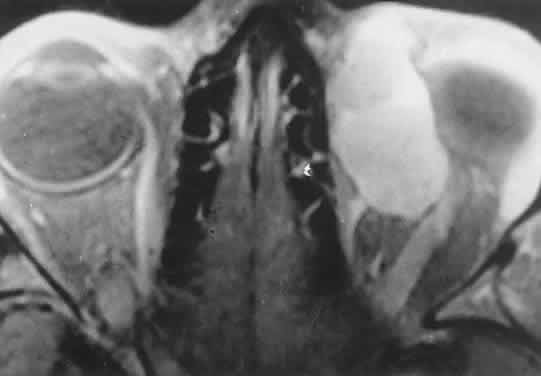

Orbital myositis may represent a greater proportion of cases of IIPT in childhood than in adulthood, and involvement of multiple extraocular muscles may occur more frequently in children than inadults. In orbital myositis, early diplopia and increased discomfort with attempted eye movement are typical symptoms. CT may show enlargement of one or more extraocular muscles in one or both orbits (Figs. 21 and 22). When a single muscle is involved, the specter of a primary or metastatic neoplasm within the muscle may be raised. However, external inflammatory signs, considerable pain and limited motility, and an explosive onset of symptoms within 24 hours all suggest orbital myositis. The uniform enlargement of the muscle, including its tendinous insertion (see Fig. 22), also helps distinguish the process from a neoplasm, which might be expected to produce a more focal, globular expansion. Echography may support the diagnosis of inflammation by showing edema in the episcleral space as a relative sonolucency between the scleral and orbital fat echoes (Fig. 23). Its CT counterpart is an increase in the radiodensity and thickness of the ocular tunica.

Fig. 22. The uniform enlargement of the left medial rectus muscle, including its tendinous insertion, is characteristic of orbital myositis.